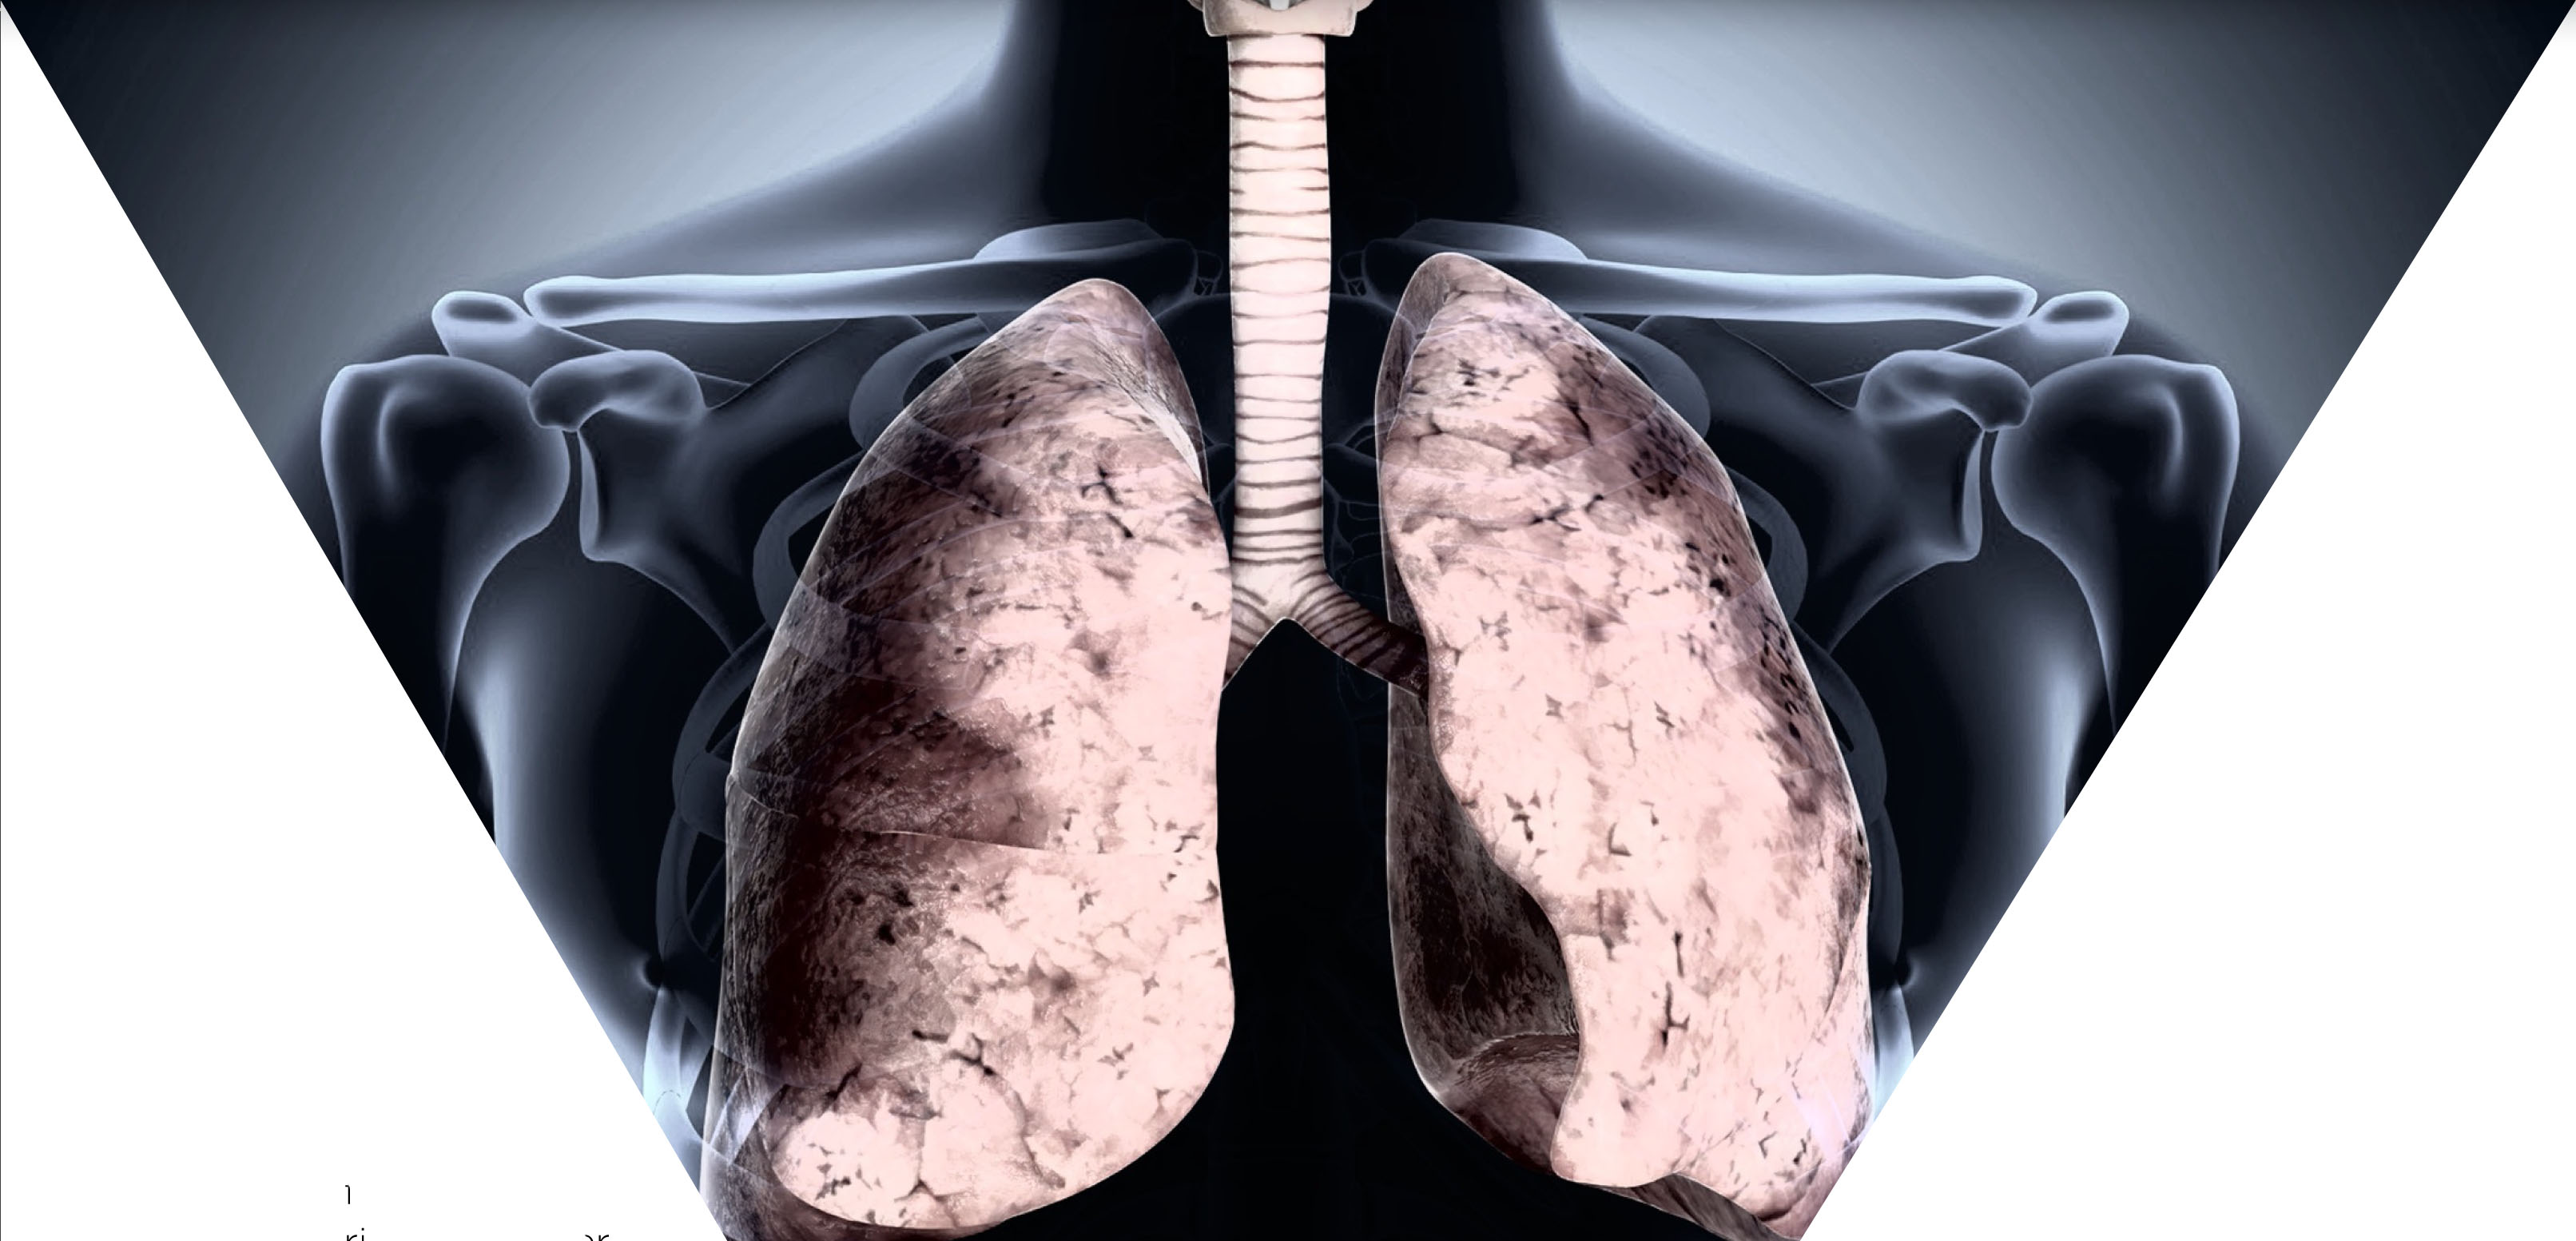

A la cicatrización o engrosamiento de los pulmones sin alguna causa conocida se le llama fibrosis pulmonar idiopática, enfermedad que se puede presentar en las personas de entre 50 a 70 años de edad y que hoy se sabe tiene un factor genético importante.

Esto se debe a que existe una gran influencia genética en el desarrollo del padecimiento, pues han sido detectados algunos genes relacionados con la presencia de tejido fibroso en pulmones.

Se ha avanzado en la comprensión de cómo funciona la fibrosis, pues se han descubierto alteraciones a nivel de telomeros; sin embargo, uno de los grandes problemas es que, hasta el momento, no se cuenta con un tratamiento y el pronóstico, en general, es de tres años de vida luego de que ha sido diagnosticada.

La rigidez en los tejidos pulmonares hace que cada vez sea más difícil respirar. Las personas afectadas pueden presentar una coloración azulada de la piel debido a la insuficiencia de oxígeno.